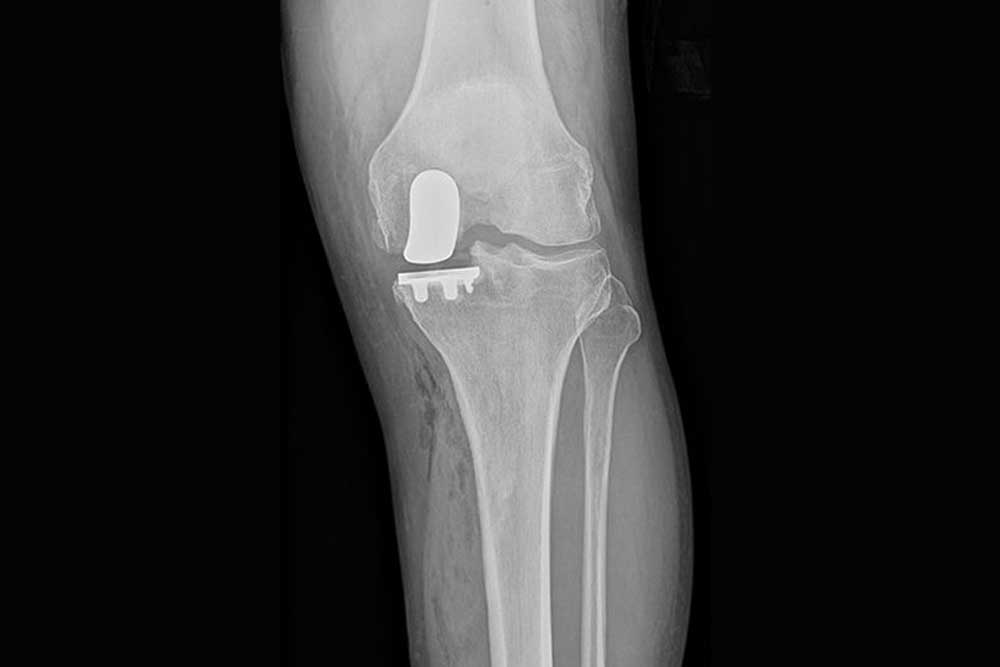

Partial Knee Replacement

Unicondylar Knee Replacement

An alternative to total knee replacement for patients suffering from osteoarthritis with damage confined to only one compartment of the knee joint.

This procedure conserves the original ligaments of the knee while replacing only the damaged part.

This procedure is minimally invasive and provides a natural feel to the patient.